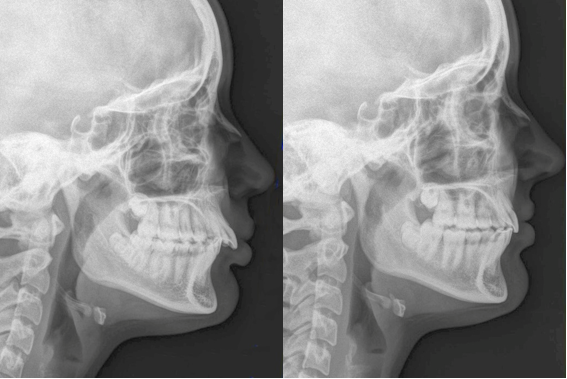

Neextrakční terapie: převislý skus

Začátek: tzv. převislý skus (stav na začátku)

Průběh léčby plným fixním aparátem

Konec po sejmutí: po sejmutí zámků z horních i dolních zubů oblouky harmonicky artikulují k sobě (zuby se dokousnou k sobě)